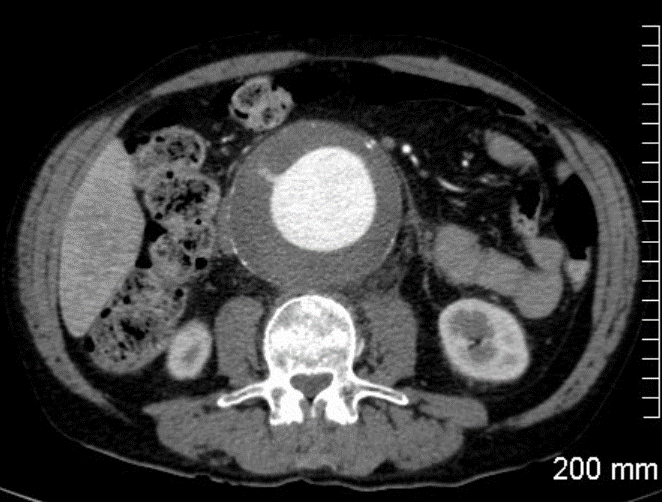

Les anévrismes de l’aorte abdominale (AAA) sont une dilatation excessive et pathologique de l’aorte dont le principal risque est la rupture. Le diamètre normal d’une aorte abdominale se situe entre 15 mm et 25 mm suivant le sexe et l’âge du patient.

bituellement, les patients porteurs d’un anévrisme ne présentent aucun symptôme. Cet AAA est découvert le plus souvent de manière fortuite lors d’un examen (échographie, scanner) réalisé pour une autre raison médicale. L’évolution naturelle d’un anévrisme est sa progression avec une augmentation de taille variable selon les individus. L’anévrisme est soit fusiforme soit sacculaire (en forme de sac). C’est dans l’aorte abdominale en dessous des reins que les anévrismes sont les plus fréquents.

Le meilleur facteur prédictif de rupture connu actuellement est le diamètre maximal de l’anévrisme. Plus l’AAA est volumineux plus il a de risques de se rompre. Cette rupture d’anévrisme peut entraîner jusqu’à 85 % de mortalité. En cas de rupture, 50% des patients toujours en vie lors de leur transfert dans un hôpital décèdent. Ce risque de rupture est faible pour les petits AAA et augmente de manière significative à partir de 55mm de diamètre qui est considéré comme le diamètre à partir duquel l’anévrisme peut ou doit être pris en charge. Au-delà de 55 mm le taux de rupture est de 10% par an et augmente avec la taille pour atteindre 30% pour les AAA supérieurs à 7cm. Dans certaines conditions (anévrisme douloureux, anévrisme sacculaire, anévrisme dans la famille, patients de sexe féminin) les AAA doivent être traités à partir de 50 mm.

La détection ciblée des AAA est recommandée chez les hommes de 65 à 75 ans fumeurs. L’échographie abdominale est l’examen de choix. Lorsqu’un AAA est détecté et que sa taille est importante, l’examen le plus utile pour bien analyser la morphologie de l’anévrisme aortique est un scanner abdominal avec injection de produit de contraste (angio-scanner). Cet examen permet de bien voir les autres artères et en particulier de mesurer la distance qui existe entre les artères rénales et l’anévrisme.

Lorsque le diagnostic d’AAA de taille significative est avéré et que l’état général du patient est satisfaisant, une intervention chirurgicale doit être proposée. Dans 60% des cas, un traitement endovasculaire est réalisable. Ce traitement endovasculaire consiste à exclure l’AAA par une endoprothèse qui est introduite par les artères fémorales au travers de la peau ou via une très courte incision aux plis de l’aine. Cette endoprothèse est un tube bifurqué synthétique renforcé par des mailles métalliques (stents). L’endoprothèse est initialement repliée dans une gaine qui est positionnée correctement au niveau de l’aorte sous contrôle radioscopique (rayons X). Cette endoprothèse est ensuite libérée de sa gaine et déployée jusqu’au niveau des artères iliaques par une manipulation à l’extérieur du patient.